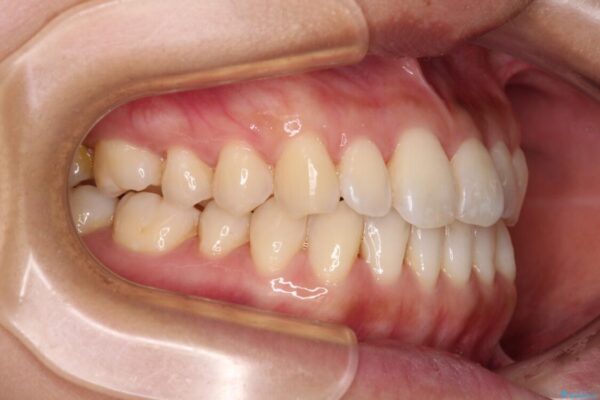

上顎前歯が捻れて前方に飛び出しており、下顎前歯もそれに沿うようにデコボコとなっていました。

IPR(歯と歯の間を削る処置)によりスペースを獲得して上下顎前歯のデコボコを改善し、飛び出している前歯が引っ込むように設定し、インビザラインにて矯正治療を行うこととしました。

• 【モニター】前歯のデコボコをインビザラインで改善 治療前画像